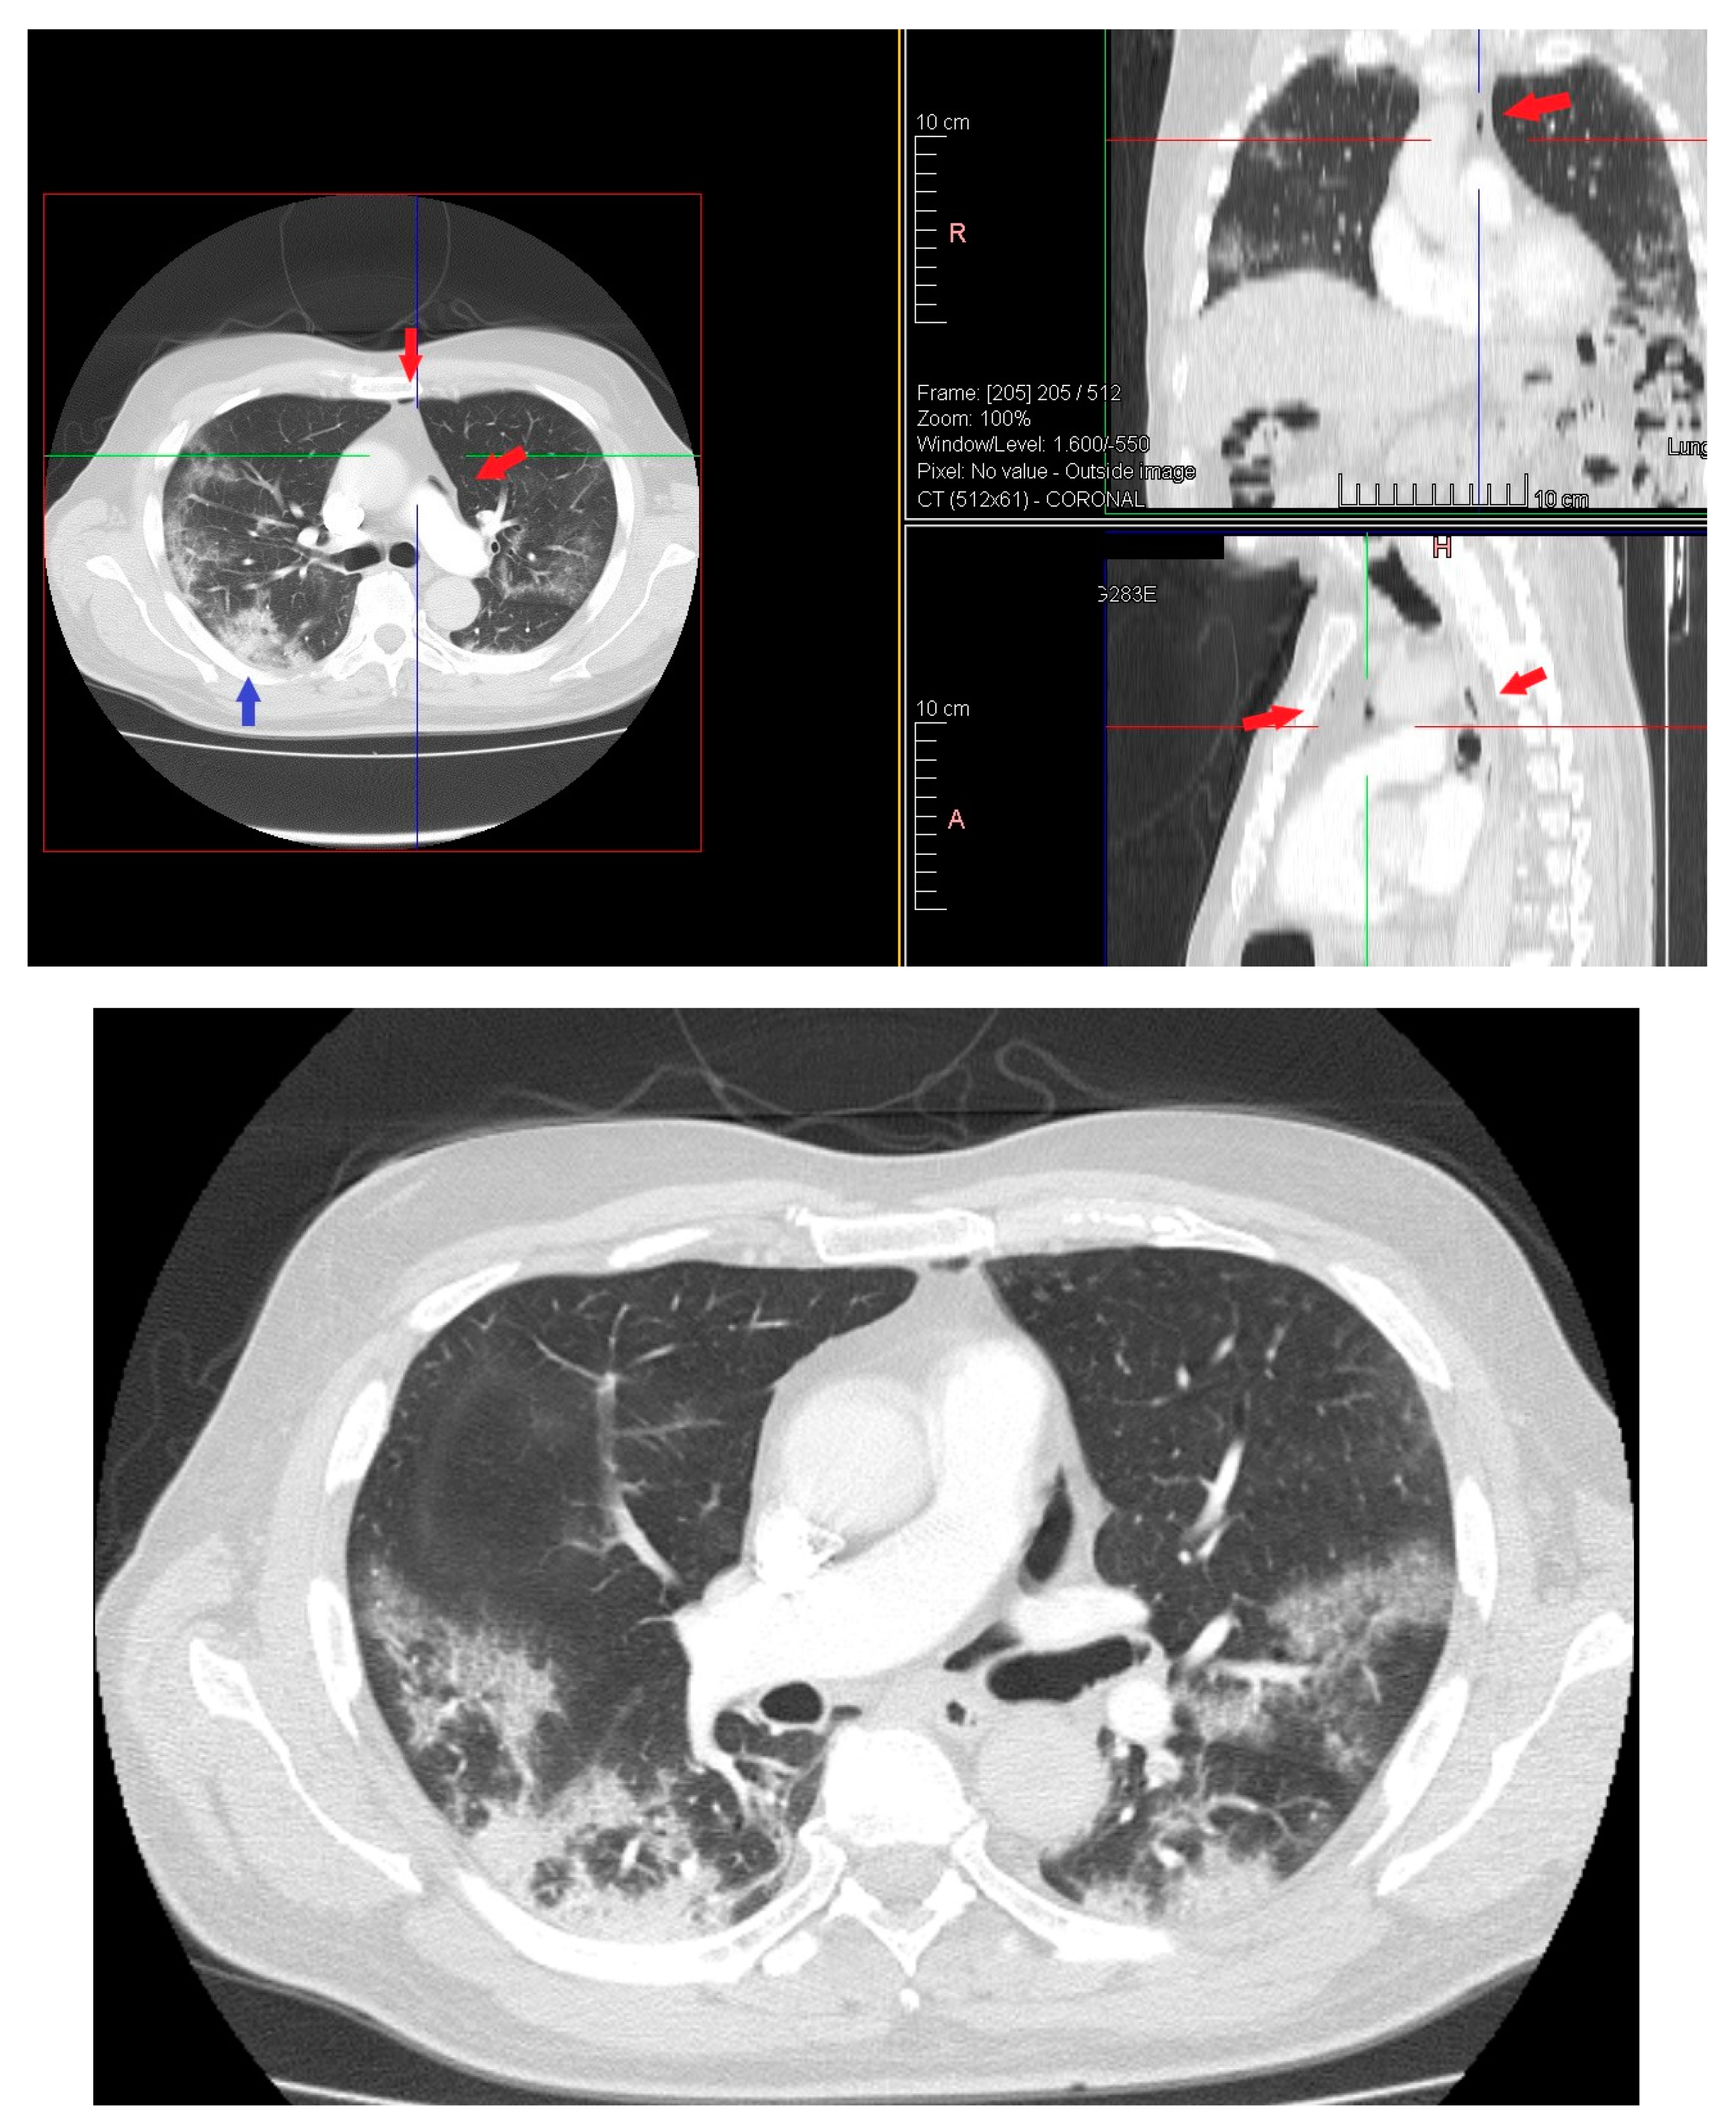

On day 22 from admission on a control HRCT was noted massive pneumopericardium in the absence of related symptoms (Figure 4). A new EKG was performed with absence of significant voltage reduction and showed sinus rhythm at HR 70 bpm. Atrioventricular conduction with PR 200 msec. Intraventricular conduction within the limits. (Figure 2B).

Figure 4. HRTC performed on day 22 from admission with evidence of massive pneumopericardium (red arrows) and severe presence of gas inside the pericardial sac (blue arrow). Detail of HRTC performed on day 22 show evidence of pneumopericardium (red arrow) and the severe presence of gas in the pericardium (blue arrow).